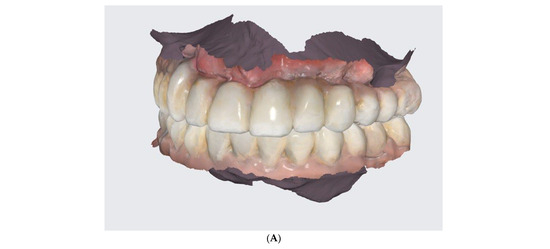

- Conduction of DSD, an I.O. scan, a 360° scan of removals, and CBCT after the healing phrase.

- The conduction of an analogue impression, an I.O. scan, a removable 360° scan, and a scanflag scan.

- The conduction of a Sheffield passive fit test of 3D-printed try-ins on a milled titanium bar.

- Final restoration delivery with occlusal equilibration.